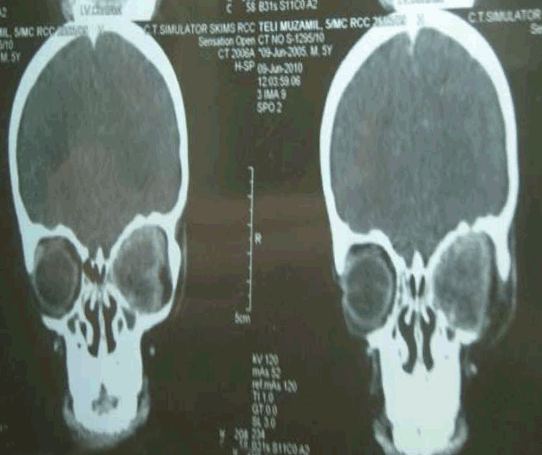

Computed tomography (CT) scan showed soft tissue density enhancing mass in the left retro-orbital region measuring 3x2.7 cm pushing the left eye ball anteriorly. The optic nerve could not be separated out and lesion seemed to be adherent to the eye ball. There was no evidence of mass in the sinuses, nasal cavities or intra- cranial cavities (figure 2).

Figure 2: Coronal CT images showing the left orbital mass.